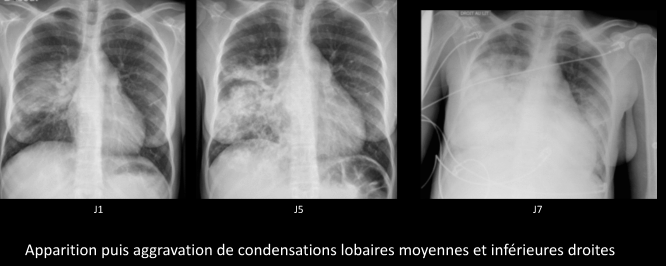

Thorax

- Acute Chest Syndrome: Infarctus pulmonaires (vaso-occlusif, parfois embols graisseux)

- Graves

- Condensations pulmonaires

- Touchant au moins un segment

- Difficile à distinguer d’une infection